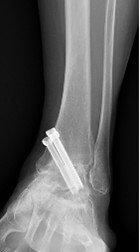

足関節固定術

術前レントゲン写真

鏡視下の骨軟骨切除

術後レントゲン